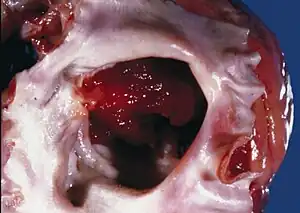

Atrial myxoma

Myxomas are usually located in either the left or right atrium of the heart; about 86 percent occur in the left atrium.[8]

Myxomas are typically pedunculated, with a stalk that is attached to the interatrial septum. The most common location for attachment of the stalk is the fossa ovalis region of the interatrial septum.[9]

An atrial myxoma may create an extra heart sound, audible to auscultation just after S2. It is most seen on echocardiography, as a pedunculated mass that is heterogeneous in appearance. A left atrial myxoma will cause an increase in pulmonary capillary wedge pressure.

The differential diagnosis include other cardiac tumors such as lipomas and rhabdomyomas (and rarely teratomas). These other tumors of the heart are typically not pedunculated, however, and are more likely to infiltrate the muscle of the heart. Cardiac magnetic resonance imaging (MRI) can help non-invasively diagnose cardiac tumors. However, diagnosis usually requires examination of a tissue sample by a pathologist.

Myxomas are usually removed surgically. The surgeon removes the myxoma, along with at least 5 surrounding millimeters of atrial septum. The septum is then repaired, using material from the pericardium.